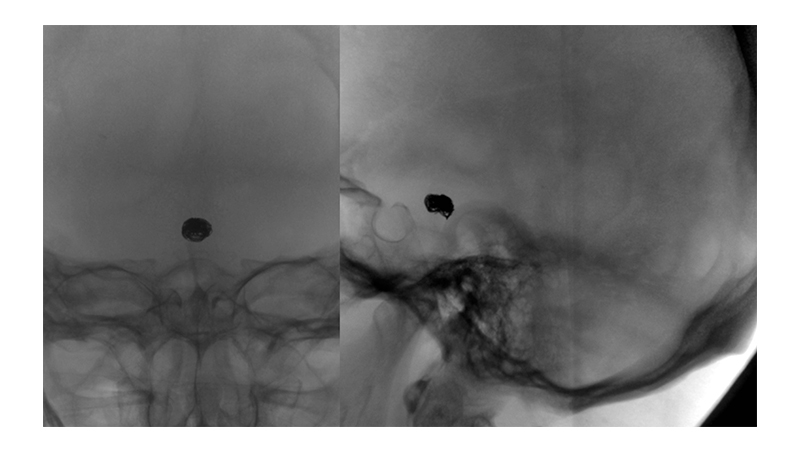

Εικόνα 1 και 2: Ραγέν ανεύρυσμα της κορυφής της βασικής αρτηρίας, το οποίο έχει ευρύτατο αυχένα. Η ασθενής ευρίσκεται ήδη σε φάση προχωρημένου αγγειοσπάσμου. Το ανώτερο τριτημόριο της βασικής αρτηρίας παρουσιάζει σημαντικό σπασμό με ελάττωση της διαμέτρου του.

Ταυτόχρονα τριχοειδική απεικόνιση του Ρ1 και Ρ2 τμήματος των οπισθίων εγκεφαλικών αρτηριών αμφοτερόπλευρα, λόγω έντονου αγγειοσπάσμου.